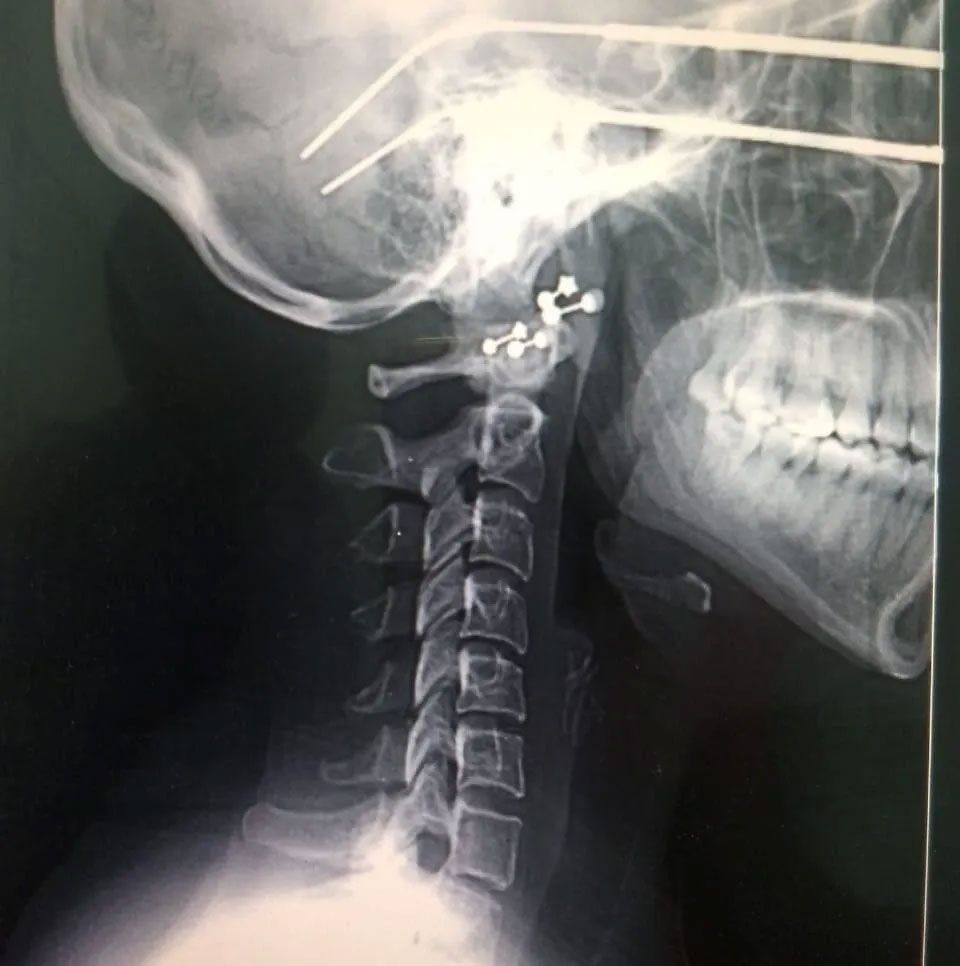

- Lesiones de columna

- Hernias de disco

- Cirugía de columna